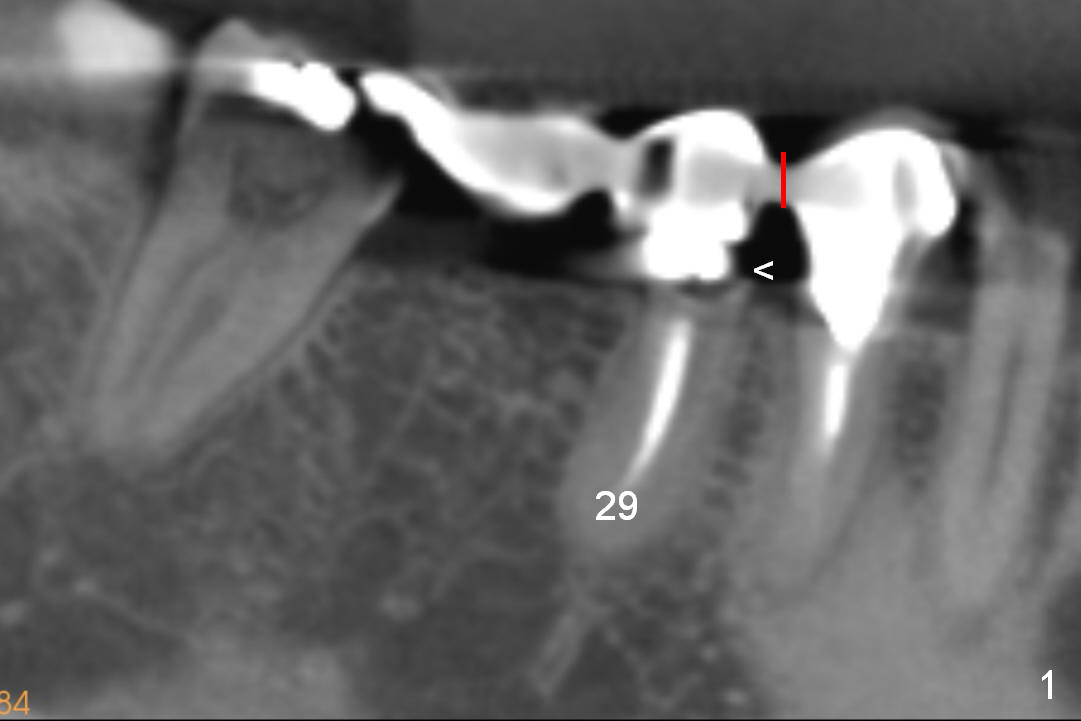

A 52-year-old lady complains of food impaction underneath #29 retainer (Fig.1). The retainer is most likely separated/fractured from its abutment (<). A section is to be made between #28 and 29 retainers (red line).